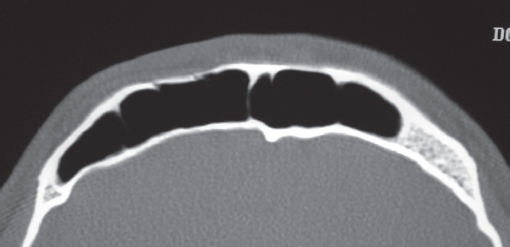

Historically, plain sinus X-rays were used to evaluate facial fractures. Thin cut (1–1.5 mm) axial computed tomography (CT) scans are now the gold standard for diagnosis of frontal sinus fractures. These images are readily reformatted into coronal, sagittal, and threedimensional (3D) reconstructions to improve the diagnostic accuracy. Axial cuts provide excellent information about the anterior and posterior table as well as pneumocephalus ( Fig. 63.5 ). Coronal reconstructions demonstrate the frontal sinus floor, orbital roof, and frontal recess ( Fig. 63.6 ). Sagittal views can assist with evaluation of frontal recess and skull base injuries ( Fig. 63.7 ). Threedimensional reconstructions can be very helpful in delineating the location of bone fragments and reducing the need for excessive dissection intraoperatively ( Fig. 63.8 ). Access to the PACS ( p icture a rchiving and c ommunication s ystem) or some type of presurgical planning software allows the surgeon to manipulate the reconstructions in space, gaining a greater understanding of depth and spatial relationships of the injury ( Video 63.1).